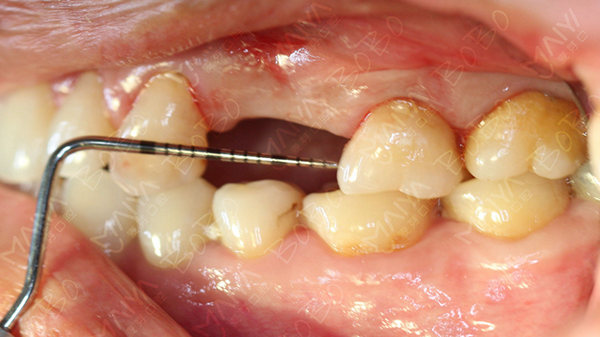

在麦芽口腔举办的"全程寻找缺牙人,免费种牙"公益活动中,赵女士成为首批免费种牙的幸运儿,麦芽口腔硕博种植专家团在对赵女士的牙齿情况做了综合检查深入分析指出,赵女士当前情况为左上4/5牙长期缺失,牙槽骨已经出现一定程度的萎缩吸收,如果长期以往不仅牙槽骨吸收越来越严重,也会影响到邻牙的健康,增加后期修复的难度。从X光全景片上,还可以看到,由于长期单侧咀嚼食物,患者脸型已经出现轻微偏脸畸形,影响了面部美观。

种牙前的牙齿情况

由于赵女士长期牙缺失,牙槽骨已经出现萎缩吸收,导致两边邻牙倾斜,因此她的牙缺失间隙在动态变小,牙齿的间隙不够种植两颗牙的位置,但是种一颗牙又显得空间有点偏大,最终专家团经综合考虑,采用麦芽MAC数字化种植技术,数字化精确导航种植,采取了种植一颗连冠修复的方式,只需一颗种植钉就可以达到修复两颗牙齿的目的,仅仅不到一个小时就帮赵女士种上了牙齿。